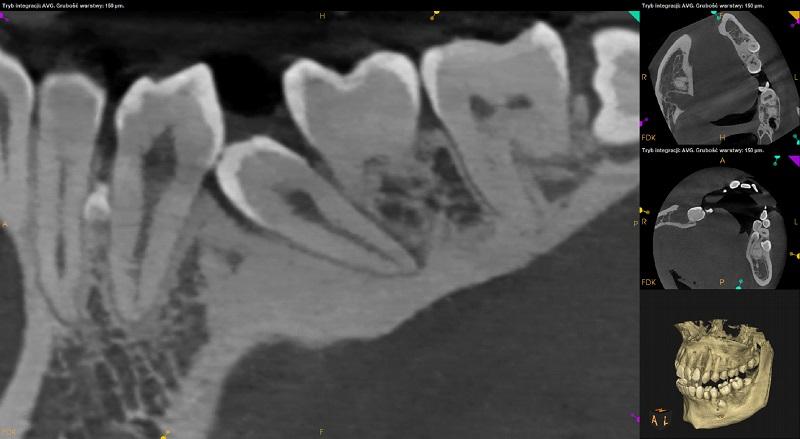

Szczęka.

Ciągłość blaszki kortykalnej dna zatok przerwana w okolicy wierzchołków korzeni zębów 17,16 po stronie prawej, 25,26 i 27 po stronie lewej.

Podejrzenie fenestracji przy zębie 12.

Pomiędzy korzeniami zębów 24 i 25 widoczny zatrzymany ząb nadliczbowy. Położony pionowo. Wierzchołek korzenia zagięty, wpukla się do swiatła zatoki szczękowej. Widoczna dyskretna resorpcja korzenia podniebiennego zęba 24 i policzkowego zęba 25.

Zęby bez znamion leczenia kanałowego. Tkanki okołowierzchołkowe bez widocznych radiologicznie cech patologicznych.

Radiologiczne przejaśnienia mogące odpowiadać próchnicy lub ubytkom w zębach: 12 – strona mezialna, 21 – strona dystalna - do dalszej diagnostyki kliniczne.